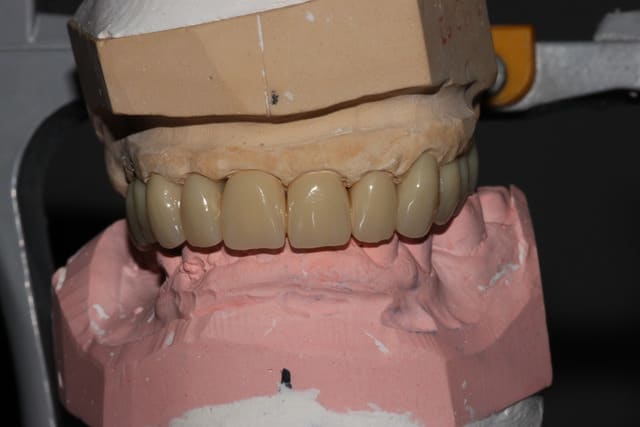

Première séance de préparation: ex 17, dépose des couronnes sans antagonistes pour se faciliter un peu le boulot de la deuxième séance, empreintes primaires.

Deuxième séance, 2h30 si mes souvenirs sont bons: préparations de tout le maxillaire, et pose du bridge pro avec une DV remontée de quelques mm. DSR manuel des poches profondes, curetage rotatif à la touati de toutes les préparations, l'accès visuel est largement simplifié.

La 12 est finalement conservée, la 24 finalement extraite.

Petit imprévu: impossible de sortir la 23, trop délabrée: je ne me sens pas de lever un lambeau lors de cette séance déjà longue, on la laisse en place pour l'instant.

Contrôle 2 jours plus tard, la nouvelle DV est bien supportée.

Les courbes occluasles ne sont pas alors idéalisées (la 36 gêne, et secteur 1 on la règlera à la plaque de fox par la suite)